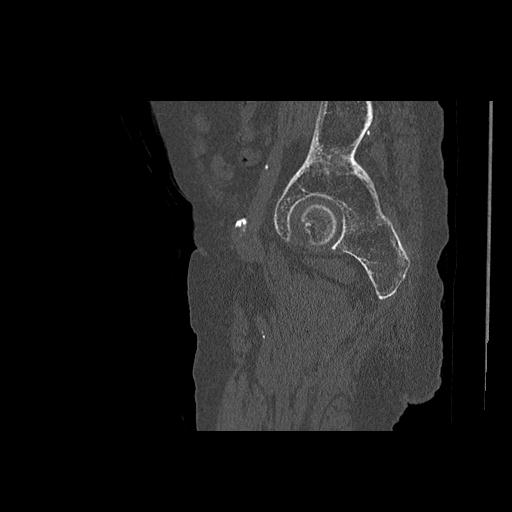

91569 3/25 両股正面とラウエン 70歳女性 人工骨頭+バンクーバー